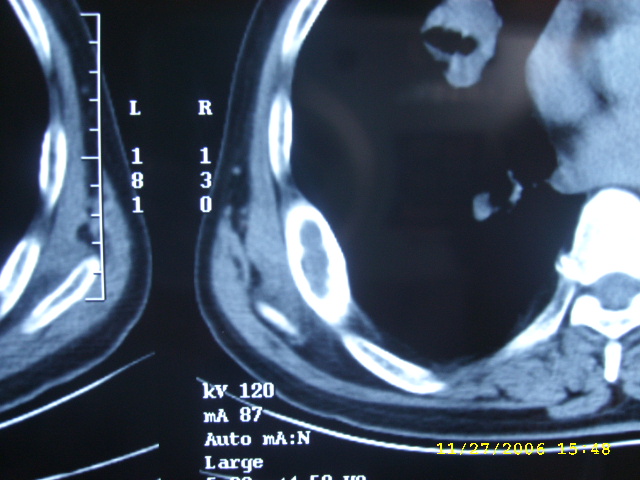

如果右肺病变与肋骨病变联系起来考虑:1右肺周围ca并肋骨转移;2:嗜酸性肉牙肿?

肺部病变先考虑周围性肺癌,肋骨病变不象破坏和转移,应考虑骨纤.一影论影.

1右肺周围ca

2骨纤维异常增埴症

肋骨应该不是转移,其为膨胀性改变,边缘增厚硬化,临近软组织未见明显异常改变,考虑骨纤等病变。

右侧周围型肺癌伴肋骨转移.

右侧肺癌,右侧肋骨转移?

肺部的病灶是比较肯定的,但肋骨骨质完整,未见破坏征象,故肋骨考虑骨纤维异常增殖症。

单纯肋骨局限性膨胀,边界清楚,皮质增生硬化,考虑:1  请详细了解病史,除外陈旧骨折.2 骨纤维异常增埴症

周围型肺癌.肋骨可能是陈旧骨折愈合.

右肺内病变考虑肺癌,右侧肋骨局部增粗,皮质增厚,髓腔增宽,有否陈旧骨折?先考虑骨纤维异常增殖症。

1.右下肺病灶周围型肺癌的可能性非常大。

2.右侧肋骨病变转移的可能性非常小,首先考虑骨母细瘤。次则考虑骨纤维异常增殖症。

建议详细询问病史,排除陈旧性骨折所致。

1.右侧周围型肺癌.

2.肋骨病变虑骨纤维异常增殖症.

肺部病变考虑周围性肺癌,肋骨病变考虑骨纤